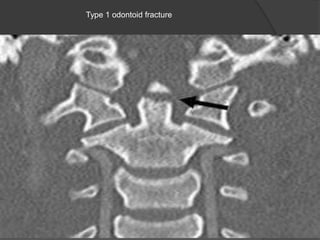

Type 1 odontoid fracture

Classification

Type I: Avulsion of the tip of

the dens where it is attached

to C1.

This is a rare fracture.

It is potentially stable.?

Type II: Through the base of

the dens.

Most common fracture.

Always unstable and poor

healing.

Type III: Fracture through the

body of the axis and

sometimes facets.

Can be unstable, but has a

better prognosis than type II

due to better healing of the

fracture which runs through

the metaphyseal body of C-2